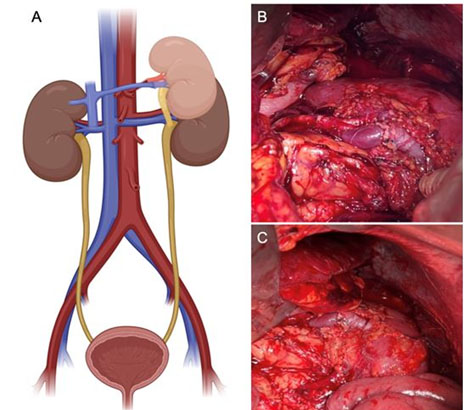

The surgical approach involved a midline laparotomy to identify the native kidney and explore options for vascular anastomosis to the patient’s renal vessels. However, a hypotrophic kidney was identified as anticipated from imaging, leading to the dissection of the splenic and suprapancreatic vessels. Due to their tortuous path, a splenectomy was performed, and an end-to-end splenorenal anastomosis of the artery and vein was executed, achieving immediate and robust reperfusion (Figure 1B and Figure 1C). The ureter was anastomosed to the native renal pelvis with the placement of a double-J catheter for drainage (Figure 1A). Intraoperatively, the warm ischemia time was 3 minutes, cold ischemia was 148 minutes, and blood loss was approximately 900 cc, necessitating one unit of packed red blood cells. In the immediate post-operative period, the patient exhibited spontaneous diuresis with a volume of 5200 cc within the first 24 hours and a creatinine decrease to 2.45 mg/dL. On post-operative day 4, a renal scan with mercaptoacetyltriglycine (MAG-3) demonstrated a clearance of 87.5 mL/min/1.73 m², with a grade 1 curve (normal perfusion and reduced excretion).

Figure 1: Representative diagram of the position and anastomosis of the renal graft (A). Photograph of the graft showing arterial and venous anastomosis to native splenic arteries (B and C).